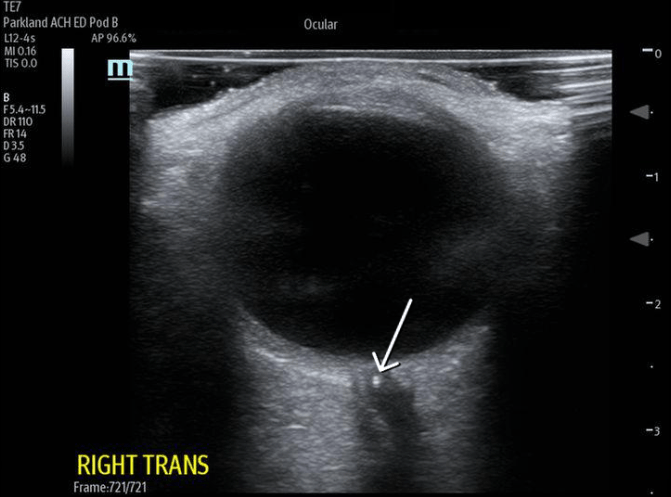

This US finding on ocular US.

What is lens dislocation?

This Us findinging indicates this disease.

What is CRAO? (Spot sign)